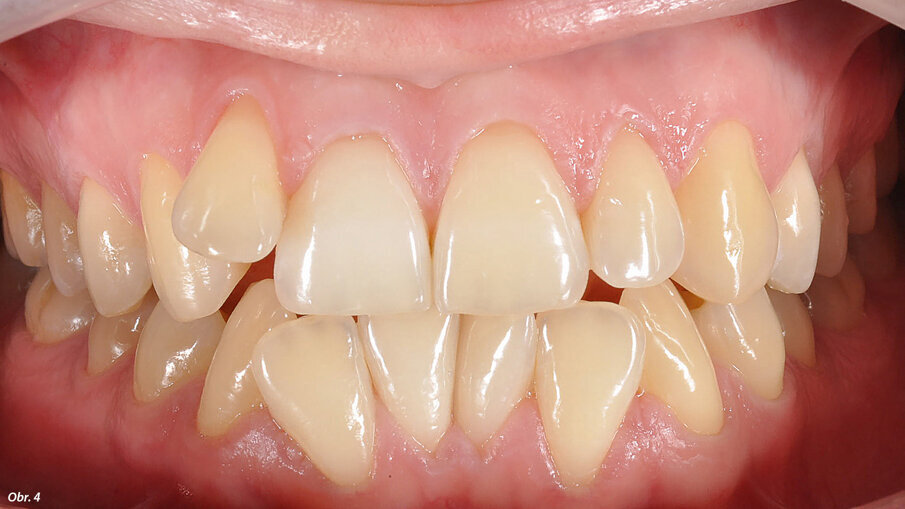

Když se 19letá Sabine S. (jméno pozměněno) objevila jako nová pacientka v naší ordinaci, stěžovala si primárně na skutečnost, že kvůli špatnému postavení zubů není schopna normálně ukusovat. Dále ji obtěžovala nevyhovující estetika rozdílného průběhu středové linie v horním a dolním zubním oblouku a postavení horního laterálního řezáku vestibulárně mimo zubní řadu (obr. 1, 2). Již během prvního sezení, které si u nás zarezervovala prostřednictvím našeho online objednávacího kalendáře, zdůraznila pacientka své funkční i estetické obtíže a trvala na jejich nápravě. Zároveň však vyjádřila určité obavy týkající se ošetření pomocí „viditelného“ ortodontického aparátu a pochybnosti, zda konečný efekt léčby bude splňovat její požadavky a představy.

Vyšetřením jsme zjistili výrazný nedostatek místa v horní i dolní frontě. Zub 12, s meziodistální šířkou 6,25 mm, byl eruptován vestibulárně zcela mimo zubní řadu se současným posunem horní středové linie doprava. Mezera mezi zuby 11 a 13 činila 1,5 mm. Nedostatek místa v dolním zubním oblouku činil 2,6 mm resp. 2,85 mm ve dvou dolních kvadrantech. V transverzálním rozměru byl oproti normě menší jak anteriorně, tak i posteriorně. Oproti tomu skus laterálně a v místě špičáků byl normální – zde jsme diagnostikovali I. třídu podle Anglea. Hloubka skusu byla 0,5 mm s tendencí k otevřenému skusu. Incizální schůdek byl 0 mm se skusem hrana na hranu u zubů 11/41 a 21/31/41. Podle Boltnových indexů byl přítomen nepoměr v šířce zubů s přebytkem „zubního materiálu“ v dolní čelisti (obr. 3–5). Při skeletální diagnostice jsme nalezli disharmonii ve velikosti čelistí s retrognátní horní čelistí a ortognátní mandibulou – III. skeletální třída s úhlem ANB -2,3° a hodnotou WITS o velikosti -3,9 mm. U vertikální analýzy byl zřejmý mírně horizontální typ růstu s hodnotou SpP/MeGo 23° a poměrem SGo/NMe 71 % na základě anteriorní inklinace horní čelisti. Interincizální úhel byl lehce zvětšený, což bylo dáno mírnou protruzí horních řezáků spolu s retrudovaným postavením dolních řezáků (obr. 6, 7).

EIntraorální fotografie počátečního stavu pacientky.